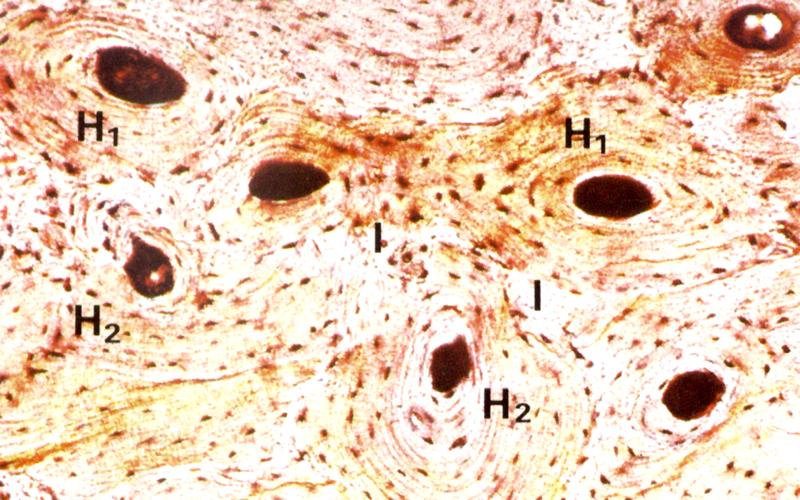

Структура грубоволокнистой костной ткани: наглядные примеры